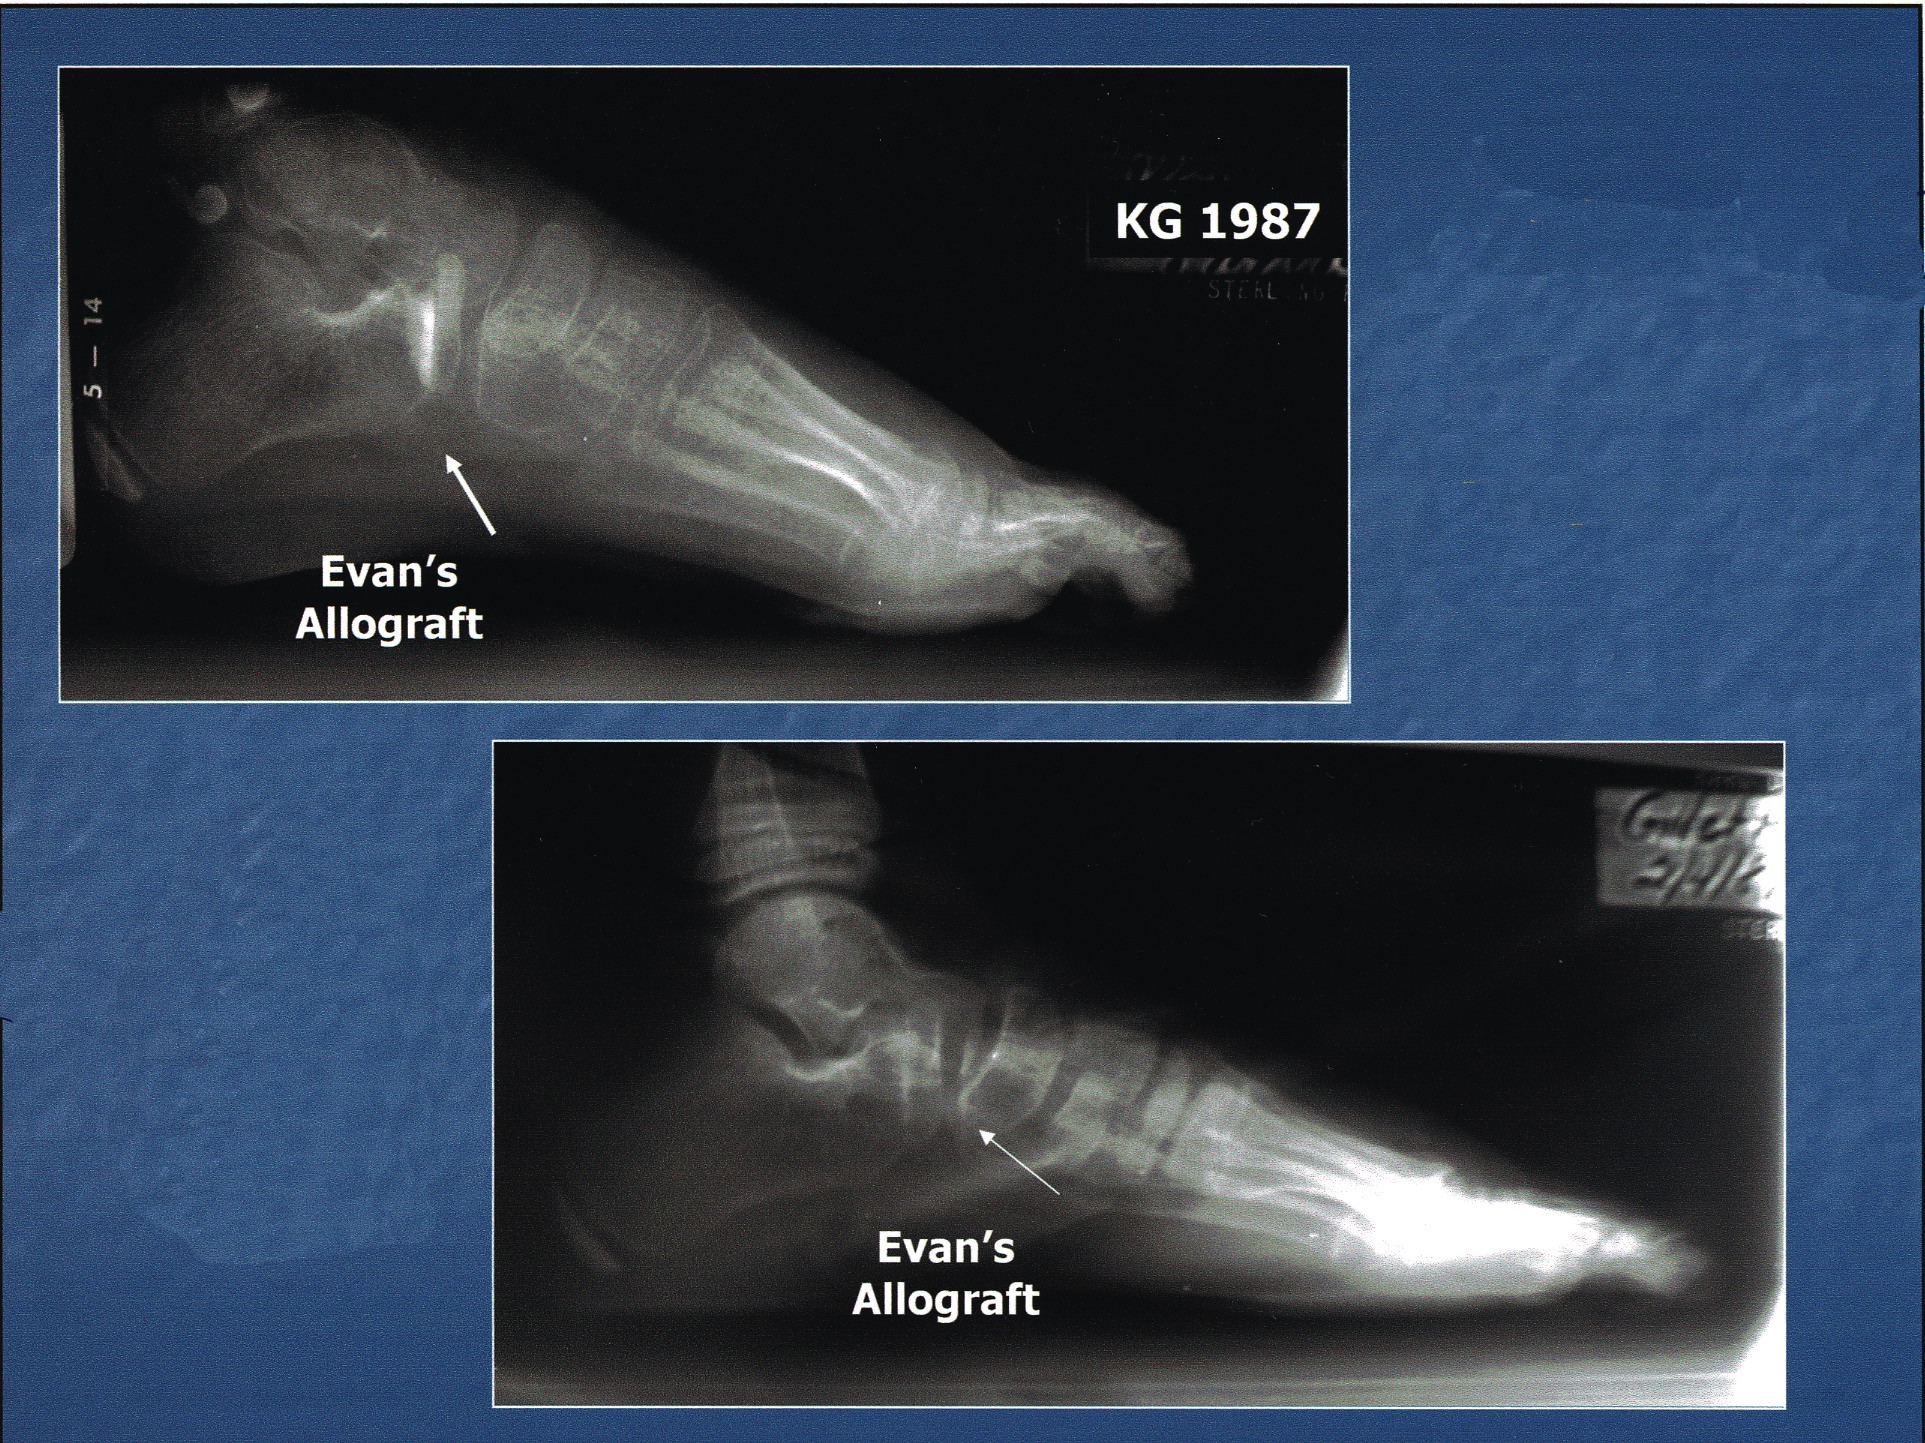

Case Study: Using Orthobiologics In Large Osseous Deficits

In this case, the patient presented with an end-stage Charcot midfoot with a chronic plantar ulceration and equinus deformity (see photo on the right). The correction entailed midtarsal joint arthrodesis, tendo-Achilles lengthening and local wound care.

Prior to compression of the limited internal beam construct, there were large osseous deficits in the talonavicular joint and calcaneocuboid joint once the surgeon debrided all of the non-viable reactive bone from the midtarsal joint.

Biologic and biophysical enhancement included an external bone stimulator, external fixation and tricalcium phosphate mixed with platelet gel concentrate and DBM. Final consolidation is evident at five months post-op (see photo on the left).

(Photos courtesy of Glenn Weinraub, DPM, FACFAS)